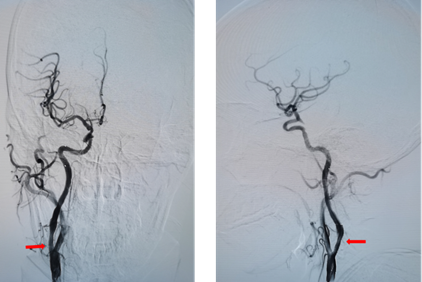

手术由神经内科孙奉辉主任和孙际典副主任医师实施,术中造影显示入颅的四条动脉(双侧颈内动脉起始部及双侧椎动脉开口)均有重度狭窄,尤其是右侧颈内动脉起始部为次全闭塞(如图),且为此次缺血性脑血管事件的责任血管,如不及时处理,病情可能随时加重。根据患者病情及家属诉求,决定先行右侧颈内动脉支架置入术,支架后血流恢复良好(如图)。术后患者症状完全消失,无明显不适。

右侧颈内动脉支架植入术后,远端血流恢复良好